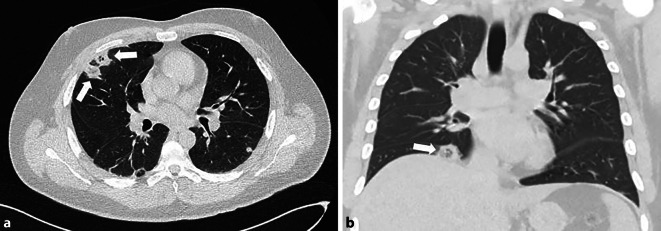

Abstract Image